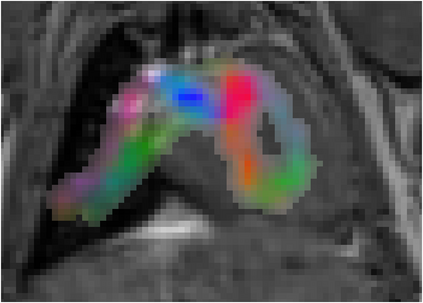

Various imaging modalities allow for time-dependent image reconstructions from measurements where its acquisition also has a time-dependent nature. Magnetic particle imaging (MPI) falls into this class of imaging modalities and it thus also provides a dynamic inverse problem. Without proper consideration of the dynamic behavior, motion artifacts in the reconstruction become an issue. More sophisticated methods need to be developed and applied to the reconstruction of the time-dependent sequences of images. In this context, we investigate the incorporation of motion priors in terms of certain flow-parameter-dependent PDEs in the reconstruction process of time-dependent 3D images in magnetic particle imaging. The present work comprises the method development for a general 3D+time setting for time-dependent linear forward operators, analytical investigation of necessary properties in the MPI forward operator, modeling aspects in dynamic MPI, and extensive numerical experiments on 3D+time imaging including simulated data as well as measurements from a rotation phantom and in-vivo data from a mouse.